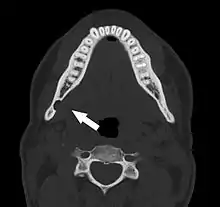

عادة ما يتم اكتشاف تجويف ستافني عن طريق الصدفة خلال التصوير الشعاعي للأسنان الروتيني.[3] في صورة الأشعة يظهر بشكل تجويف محدد أحادي مستدير منفذ للأشعة، يتراوح حجمه بين 1 و 3 سم، عادة بين العصب السنخي السفلي (IAN) والحدود السفلية للفك السفلي الخلفي بين الضروس وزاوية الفك. انها واحدة من عدد قليل من الآفات المشعة التي يمكن أن تحدث تحت العصب السنخي السفلي. الحدود محاطة بشكل جيد ولن يكون لها أي تأثير على الهياكل المحيطة. سيُظهر التصوير المقطعي المحوسب (CT) تجويفًا ضحلًا عبر القشرة الوسطية للفك السفلي مع حافة محاطة ولا توجد تشوهات في الأنسجة الرخوة، باستثناء جزء من الغدة تحت الفك السفلي. يمكن أن تخلق الأورام مثل السرطان الحرشفي الخلايا النقيلي إلى العقد اللمفاوية تحت الفك السفلي أو ورم الغدد اللعابية، مظهرًا مشابهًا ولكن نادرًا ما يكون لها حدود محددة بشكل جيد ويمكن عادةً أن يتم تحسسها في أرضية الفم أو مثلث تحت العنق تحت الفك السفلي ككتلة صلبة. التصوير المقطعي المحوسب والفحص السريري عادة ما يكون كافيا للتمييز بين هذا وتجويف ستافني. يميل تجويف ستافني أيضًا إلى عدم الزيادة في الحجم أو التغيير في المظهر الشعاعي بمرور الوقت (ومن هنا يأتي المصطلح "كيس عظمي ثابت")، ويمكن استخدام هذا للمساعدة في تأكيد التشخيص. لا يتطلب الأمر عادة خزعة من الأنسجة، ولكن إذا تم عملها فإن مظهر الأنسجة هو عادة أنسجة الغدة اللعابية الطبيعية. في بعض الأحيان تكشف عينة من تجويف ستافني عن تجويف خالٍ (ربما بسبب إزاحة الغدة في وقت أخذ الخزعة)، أو محتويات أخرى مثل الأوعية الدموية أو الدهون أو اللمف أو الأنسجة الضامة. قد يتطلب تجويف الفك السفلي اللساني الأمامي خزعة للتشخيص الصحيح في هذا المكان الغير عادي. قد يركب التجويف المنفذ للأشعة على الأسنان الأمامية السفلية ويحدث خطأ تشخيصي بأنه لآفة سنية المنشأ. في بعض الأحيان قد يقطع التجويف الحد السفلي للفك السفلي، وقد يكون جسه ممكن. قد يستخدم أحيانا تصوير القناة اللعابية للمساعدة في إظهار الأنسجة الغدة اللعابية داخل العظام.